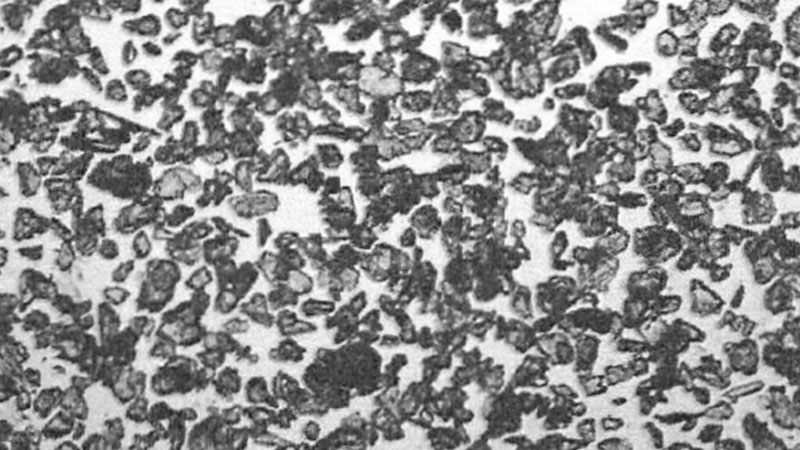

“The most important clinical implication of our study is that largeparticle talc can safely be used for pleurodesis. Other talc preparations should not be used for this indication.”

Janssen et al.: Safety of pleurodesis with talc poudrage in malignant pleural effusion: a prospective cohort study. Lancet 2007; 369: 1535-1539